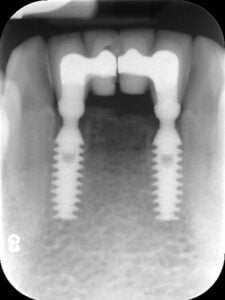

Odbudowa protetyczna 4 dolnych zębów siecznych na implantach BICON – zdjęcie RTG

Odbudowa protetyczna 4 dolnych zębów siecznych na implantach BICON